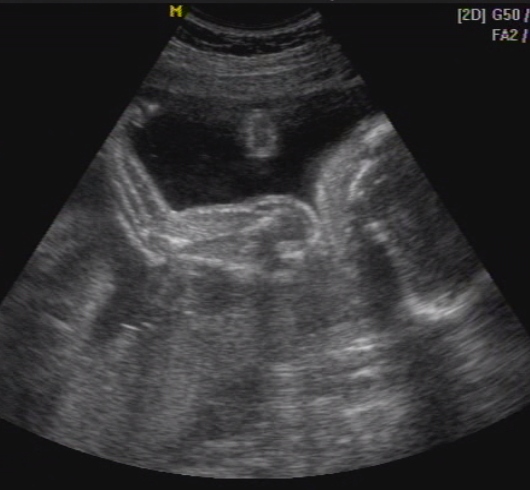

MPocAug12

MPocAug12 MBabuci1

MBabuci1 MBabuci2

MBabuci2

mosolygós kép...

mosolygós kép...